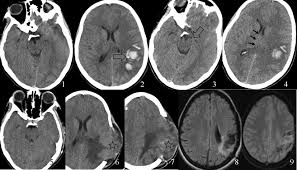

Common subtypes include transverse sinus thrombosis and superior sagittal sinus. What causes cerebral venous sinus thrombosis? Cerebral venous sinus thrombosis occurs when a blood clot forms in the brain's venous sinuses. Cerebral venous thrombosis (cvt) is an uncommon disorder in the general population. (iii) clinical and radiological features of brain lesions in csvt compared with arterial stroke, and (iv) a low threshold for ct or mr venography in children with acute neurological symptoms is essential.

Magnetic resonance imaging of cerebral venous sinus thrombosis. (iii) clinical and radiological features of brain lesions in csvt compared with arterial stroke, and (iv) a low threshold for ct or mr venography in children with acute neurological symptoms is essential. Can cerebral venous sinus thrombosis be prevented? Thrombosis of cerebral veins and venous sinuses is a rare disease, which accounts for less than 1% of all cases of stroke. Cerebral venous thrombosis (cvt) is an uncommon disorder in the general population. A thrombotic obstruction of the cerebral veins and/or related anatomical structures (dural sinuses) which drain blood from the brain. Cerebral venous thrombosis accounts for less than 1 % of all cases of stroke worldwide. A case report and review of the literature. Cerebral venous and sinus thrombosis (cvst) is a rare disease responsible for less than 1% from the total of avc causes (bajenaru, 2010). Cerebral venous sinus thrombosis occurs when a blood clot forms in the brain's venous sinuses. Cerebral venous thrombosis (cvt) refers to occlusion of venous channels in the cranial cavity, including dural venous thrombosis, cortical vein although not used routinely in clinical practice, whole brain ct perfusion may assist in establishing the diagnosis of cvt by detecting perfusion. Common subtypes include transverse sinus thrombosis and superior sagittal sinus. Cerebral venous thrombosis (cvt) or cerebral venous sinus thrombosis (cvst):